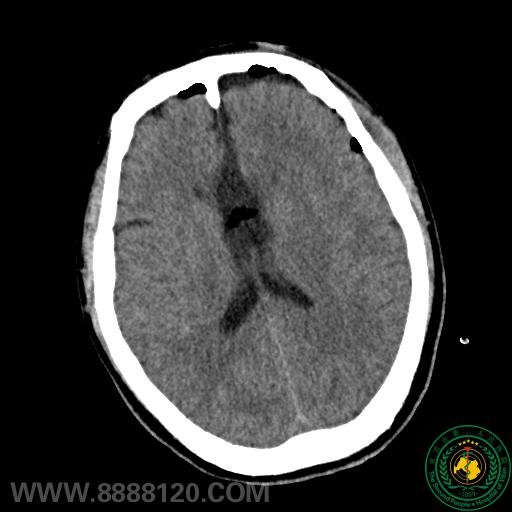

我科成功开展全市首例难治性癫痫胼胝体切开术

我科成功开展全市首例难治性癫痫胼胝体切开术6675